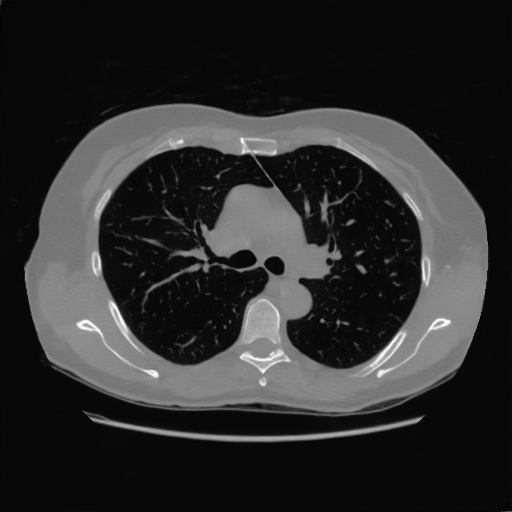

IV-F Real CT Reconstruction

To further verify the effectiveness of the RBP-DIP framework, real CT data from the Finnish Inverse Problem Society [49, 50] was used to validate our algorithm. The few-view and limited-angle reconstruction results are shown in Figure 12. Due to the lack of available training sets, pre-trained models were not included in the experiments. Different from the previous experiment, data from Finnish Inverse Problem Society is highly noisy. However, it is still evident that the RBP-DIP outperforms all other algorithms in all experiments, even under high noise and highly ill-posed conditions.

SNR/SSIM

10.94dB/0.41

13.60dB/0.40

16.25dB/0.53

10.79dB/0.45

13.91dB/0.47

16.49dB/0.57

9.74dB/0.30

12.22dB/0.26

14.46dB/0.42

(a) Reference

8.41dB/0.34

(b) ASD-POCS

12.77dB/0.31

(c) DIP

14.59dB/0.45

(d) RBP-DIP